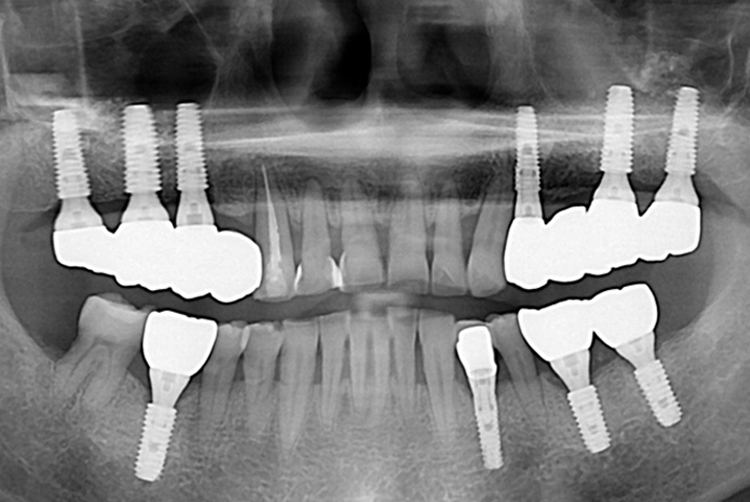

d79ef15541afd4a3965ea51756bf1235.jpg

치료전 : 2019-10-09